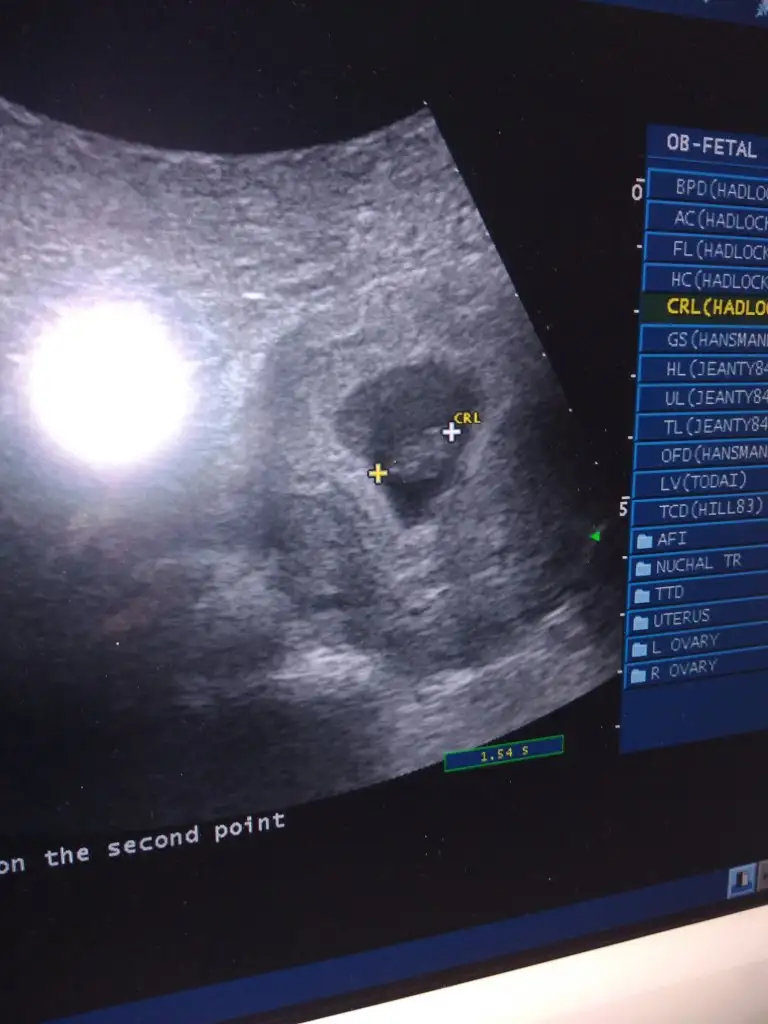

Merhabalar Rica etsem banada yorum yaparmisiniz 10 haftalik

• received_3491652160875906.webp

received_3491652160875906.webp

19,2 KB · Görüntüleme: 52